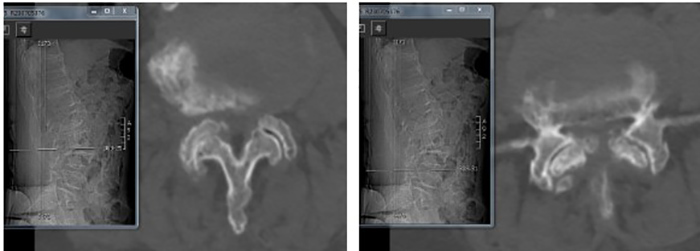

陈瑞松副主任医师接诊后,经过详细询问病史、全面查体,并结合影像学检查,诊断为腰椎椎管重度狭窄症。考虑到张阿婆年事已高,有高血压、冠心病、糖尿病、骨质疏松病史,陈瑞松副主任医师建议其采用微创手术治疗。据介绍,相较于常规开放手术,脊柱微创手术有创伤小、出血少、恢复快等优点,是高龄患者的福音。

术前影像

经过详细的术前评估和完善的术前准备,陈瑞松带领团队为张阿婆进行一个节段的单侧入路双侧减压(ULBD)手术及一个节段的双侧入路270度减压手术,仅切开了三个7毫米的小切口,一个多小时就顺利完成手术。